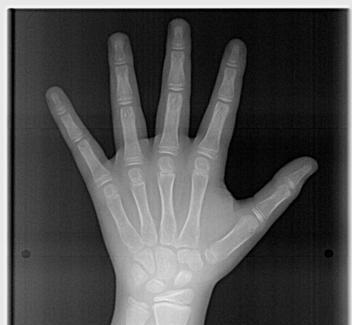

Rx Carpograma

Es una radiografía que sirve para observar factores de crecimiento en los niños.